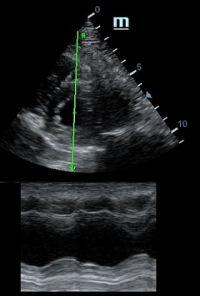

Но как же провести стандартные измерения в М-режиме, если мы его не использовали? На помощь приходит функция Free Xros M – анатомический М-режим. Имея записанную в память прибора видео петлю, мы можем провести линию М-режима в любом месте, при этом корректируя изначально не оптимальный угол.

Возможности применения функции многогранны: от измерения толщины стенок левого желудочка, движения створок митрального клапана и кооптации нижней полой вены до оценки сократимости миокарда как глобально, так и по сегментам.

Показатели УЗ сканирования в М-режиме

Какие показатели можно использовать при анатомическом М-режиме помимо привычных срезов через конец створок митрального клапана или синуса Вальсальве?